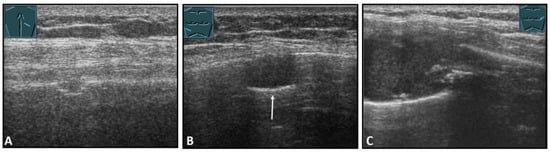

Figure 4.

Illustration of different patterns of traumatic rib fractures: (A) major step formation with hematoma (arrow); (B) minor step formation; (C) minimal contour disruption (arrow) with small hematoma; (D) small impression (arrow) with hematoma; and (E) long-standing fractures with bone consolidation.